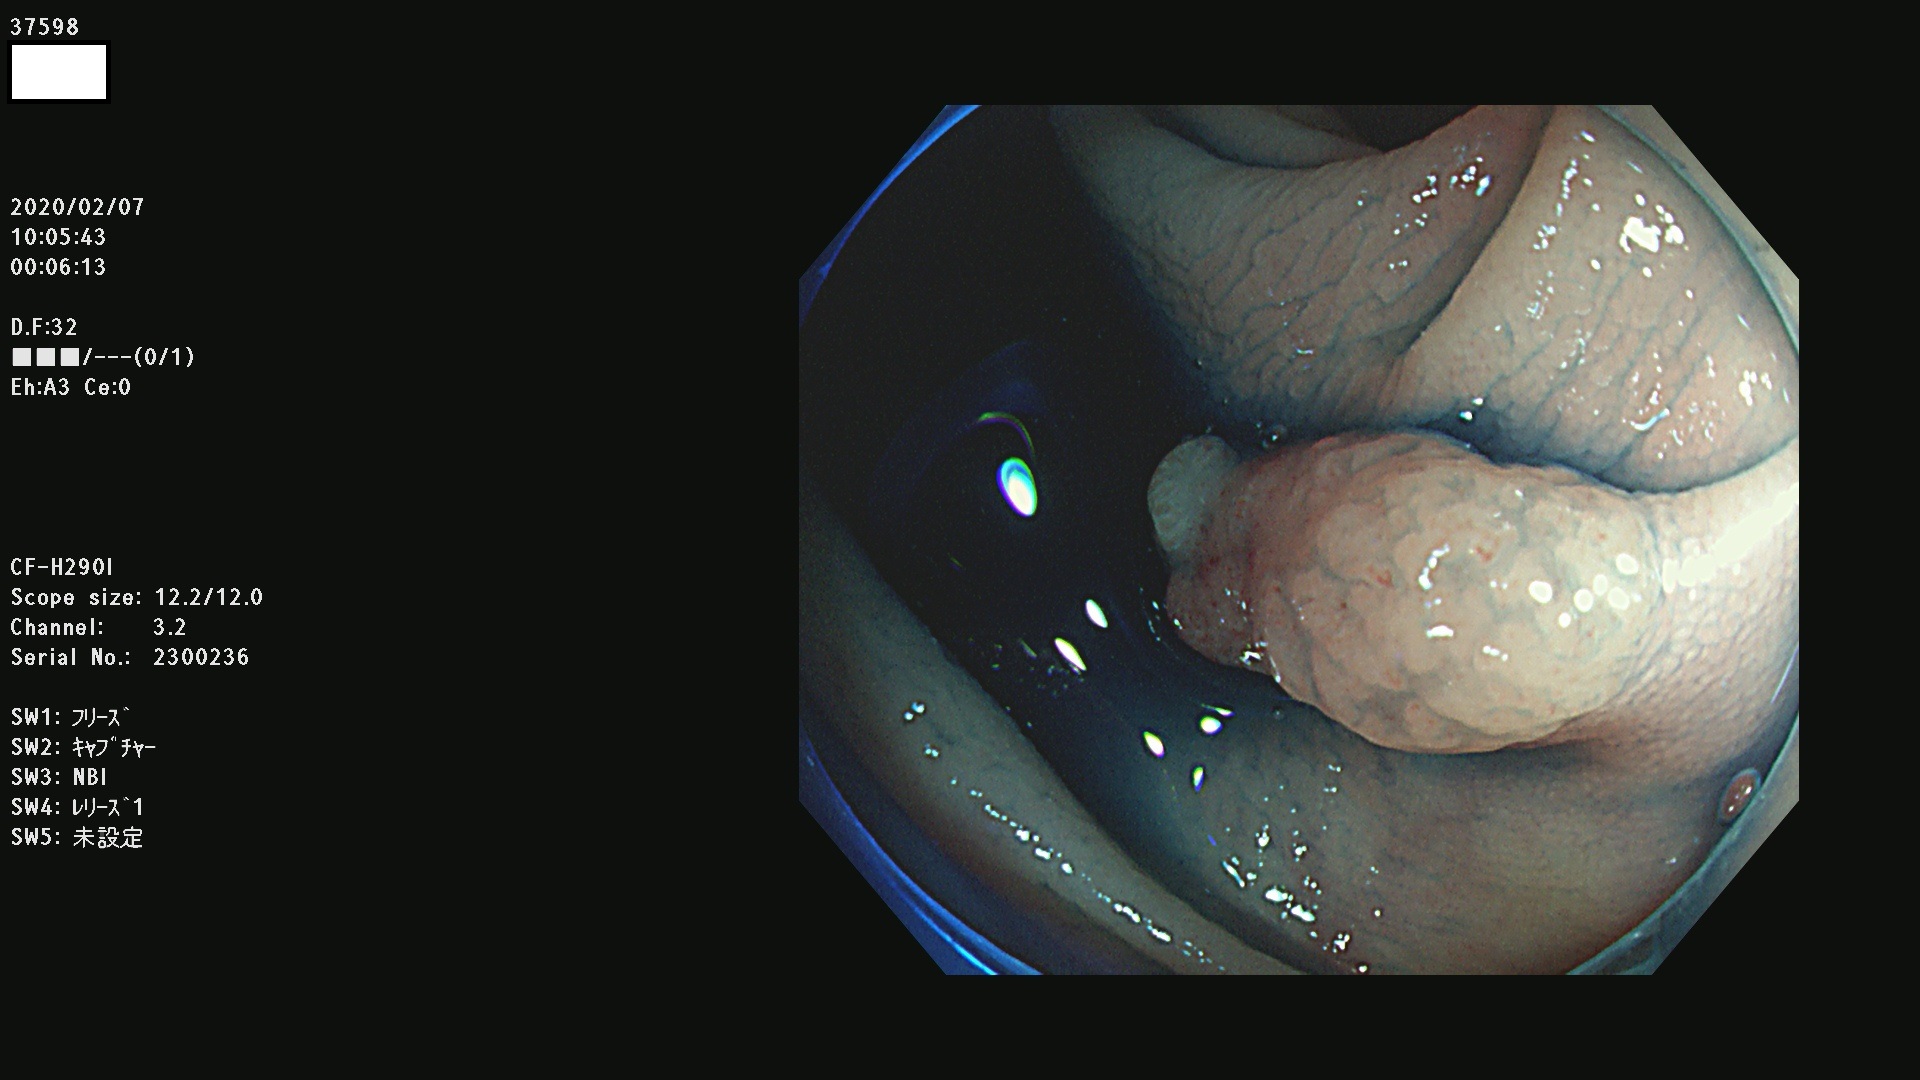

腺腫発見率 67 % (カルテ番号 37500〜37599の100名の方の検査結果で集計)大腸癌検診最新情報

以下のカルテ番号の方に腺腫(Adenoma,Group3〜5)が見つかりました(集計法)

37500 37502 37503 37505 37508 37509 37510 37511 37512 37513 37514 37517 37519 37520 37521 37525 37526(SSAPのみ) 37527 37528 37529 37531 37532 37533 37534 37536 37538(SSAPのみ) 37539 37541 37542 37543 37547 37548 37549(SSAPのみ) 37550 37552 37555 37556 37561 37562 37563(SSAPのみ) 37564 37565 37566 37567 37568 37570 37571 37572 37573 37574 37575(SSAPのみ) 37576 37577 37579 37580 37582 37583 37586(SSAPのみ) 37587 37588(SSAPのみ) 37590 37593(SSAPのみ) 37594 37596 37597(SSAPのみ) 37598 37599

発見困難で危険性の高い平坦型病変(上記100名より抽出) ![]()